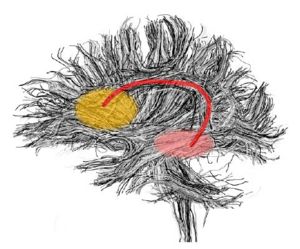

These labelmaps ('caseD00XXX-FS-arcuate-final.nhdr') were created using automatic gray matter parcellation in Freesurfer and coregistered in Slicer to corresponding DTI dataset. The labelmaps were dilated in Slicer to increase coverage of gray matter.

Figure 12. Gray matter ROI's for Arcuate Fasciculus tractography

Figure 13. Gray matter ROIs (right side) in 3D

The color coding of the resulting ROIs is as follows:

ROI 1: Superior Temporal Gyrus - Left(5) - Right(6)

ROI 2:Inferior Frontal Gyrus- Left(13) - Right (14)

Second generation ROI

The ROIs were generated based on the FreeSurfer cortical parcellation, dilated to include the underlying white matter and mapped back into the DWI-Ed-EPI space:

left side: source: Inferior Frontal Gyrus and Sulcus (label #2) ; sink: Superior Temporal Gyrus and Sulcus(label #7)

right side: source: Inferior Frontal Gyrus and Sulcus (label #8); sink: Superior Temporal Gyrus and Sulcus (label #9 ).